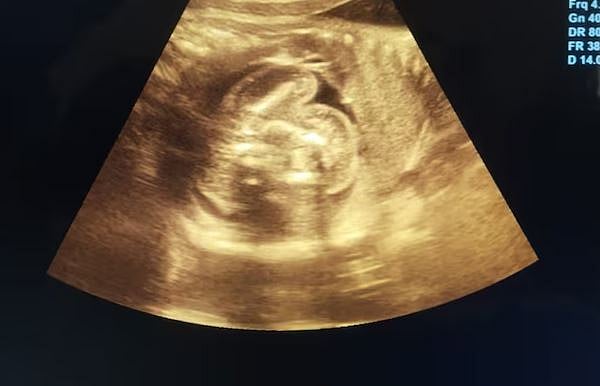

மகாராஷ்டிரத்தில் ஓர் கர்ப்பிணிப் பெண்ணிற்கு அரிய வகையான ‘கருவினுள் கரு’ எனும் நிலை உண்டாகியிருப்பதை மருத்துவர்கள் கண்டுபிடித்துள்ளனர்.

புல்தானா மாவட்டத்தின் பெண்கள் மருத்துவமனையில் 35 வாரங்கள் கர்ப்பிணியான 32 வயதுடைய பெண்ணிற்கு சோனாகிராபி சோதனை செய்யப்பட்டது. அப்போது, அவருக்கு கருவினுள் கரு (ஃபீடஸ் இன் ஃபீட்டூ) எனும் அரிய வகையான நிலை உருவாகியுள்ளது கண்டுபிடிக்கப்பட்டது.

அதாவது, ஓர் பெண்ணின் வயிற்றுக்குள் உண்டாகியுள்ள குழந்தையின் உடலினுள் மற்றொரு முழு வளர்ச்சியடையாத குறைபாடுடைய கரு உருவாகியிருக்கும் நிலைதான் இது எனக் கூறப்படுகிறது.

இதுகுறித்து, அந்த மருத்துவமனையின் மகப்பேறு மருத்துவர் பிரசாத் அகர்வால் கூறியதாவது, கர்ப்பிணிப் பெண்ணுக்கு ஏற்பட்டுள்ள இந்த நிலையானது 5 லட்சத்தில் ஒருத்தருக்கு மட்டும் நிகழக்கூடிய அரிய வகையான மருத்துவ நிலை என்றும், இது வரை உலகளவில் வெறும் 200 பேருக்கு மட்டுமே இந்த நிலை உண்டாகியது என்றும் அவர் தெரிவித்துள்ளார்.

பெரும்பாலும், குழந்தை பிறந்த பின்னரே கண்டறியப்படும் இந்த நிலை இந்த பெண்ணிற்கு பிரசவத்திற்கு முன்னரே கண்டுபிடிக்கப்பட்டுள்ளது. இந்தியாவில் இது வரை 10 முதல் 15 பேருக்கு மட்டுமே இந்த வகையான கர்ப்பம் உண்டாகியுள்ளதாகக் கூறப்படுகிறது.

முன்னதாக, 8 மாத கர்ப்பிணியான அந்த பெண்ணின் கருவில் உண்டாகியுள்ள குழந்தையின் வயிற்றுப் பகுதியில் ’கரு’ போன்ற உருவம் சோனோகிராப்பி சோதனையில் கண்டுபிடிக்கப்பட்டு கதிரியக்க நிபுணரால் உறுதி செய்யப்பட்டுள்ளது.